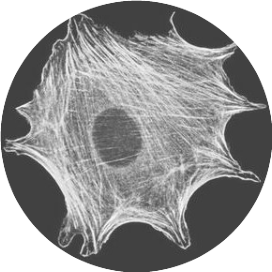

力学现象对一些基本细胞进程的正常运作至关重要,力学载荷可以作为胞外信号来调节细胞功能。危及人类健康的几种主要疾病,如骨质疏松症、动脉粥样硬化和癌症等,均与力学感知或功能障碍有关。 文章来源为网络搜集,如有侵权请联系15336881895谢谢

肿瘤生长和发展的生物物理学:从单一机械敏感分子到机械医学